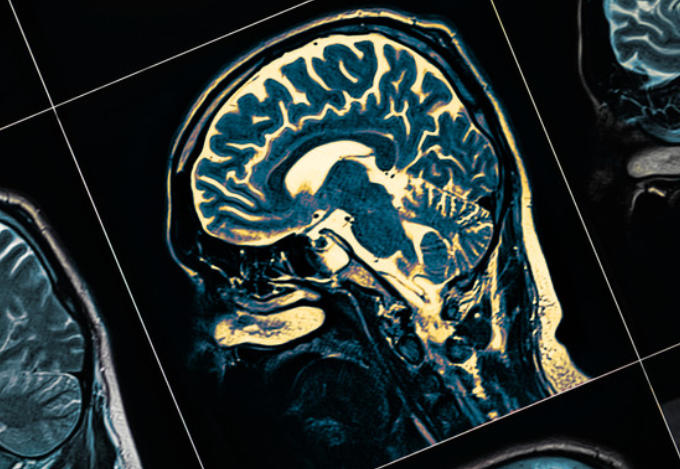

파킨슨병은 신경성 질환으로, 움직임 장애, 근육 경직, 떨림 등의 증상을 일으킵니다.

이 수술은 신경 세포의 활동을 조절하기 위해 뇌 내부에 전극을 삽입하는 방법입니다.